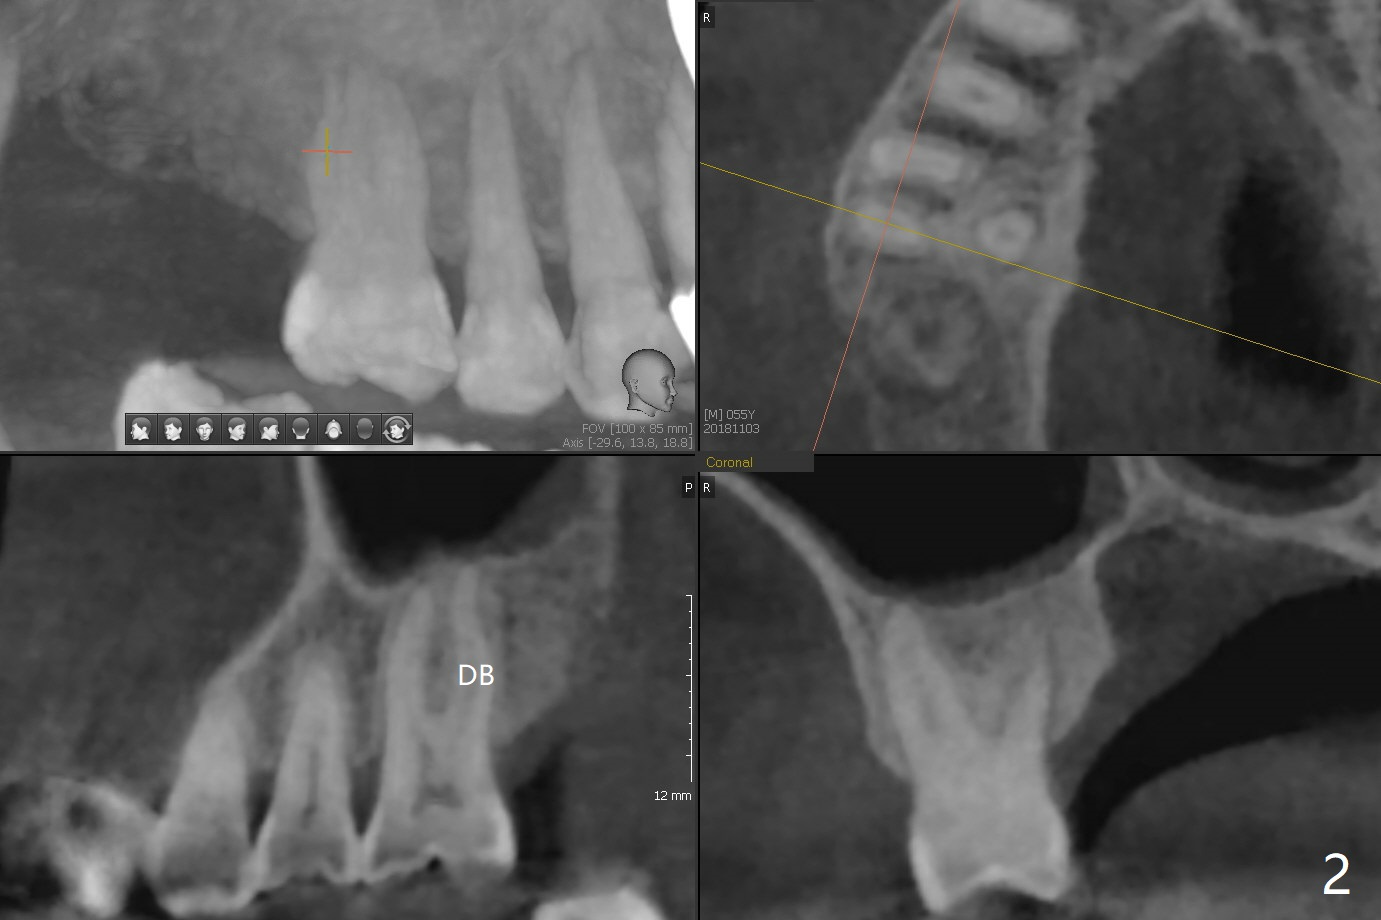

DB:远中颊侧,似乎穿过窦底,术中牙槽窝低软,但是没有漏气。